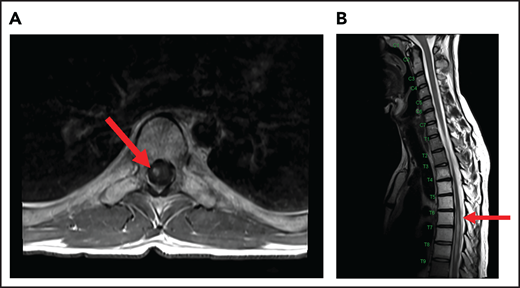

Spinal cord compression can cause severe and permanent neurologic deficits and must be diagnosed and treated emergently to reverse symptoms and prevent devastating sequelae. Epidural lesions caused by lymphoma involvement of the vertebral bodies of the spine or paravertebral lymph nodes can lead to spinal cord compression (Figure 2). In a retrospective study of 131 patients with primary bone lymphoma, one-third of the patients had involvement of the spine leading to cord compression in half of them.11 Most patients present with back pain, although neurologic symptoms including paralysis, sensory loss, and bladder and bowel dysfunction can evolve rapidly. Delayed diagnosis and treatment can result in permanent neurologic deficits. Diagnosis is typically made with MRI of the spine. Dexamethasone can improve neurologic symptoms and signs until definitive treatment, including chemotherapy and/or radiation can be instituted. Occasionally, patients may need neurosurgical intervention to maintain stability of the spine.

MRI of the cervical and thoracic spine of a patient with epidural spinal cord compression. A sagittal T2 image shows epidural involvement by NHL with compression of the underlying spinal cord.